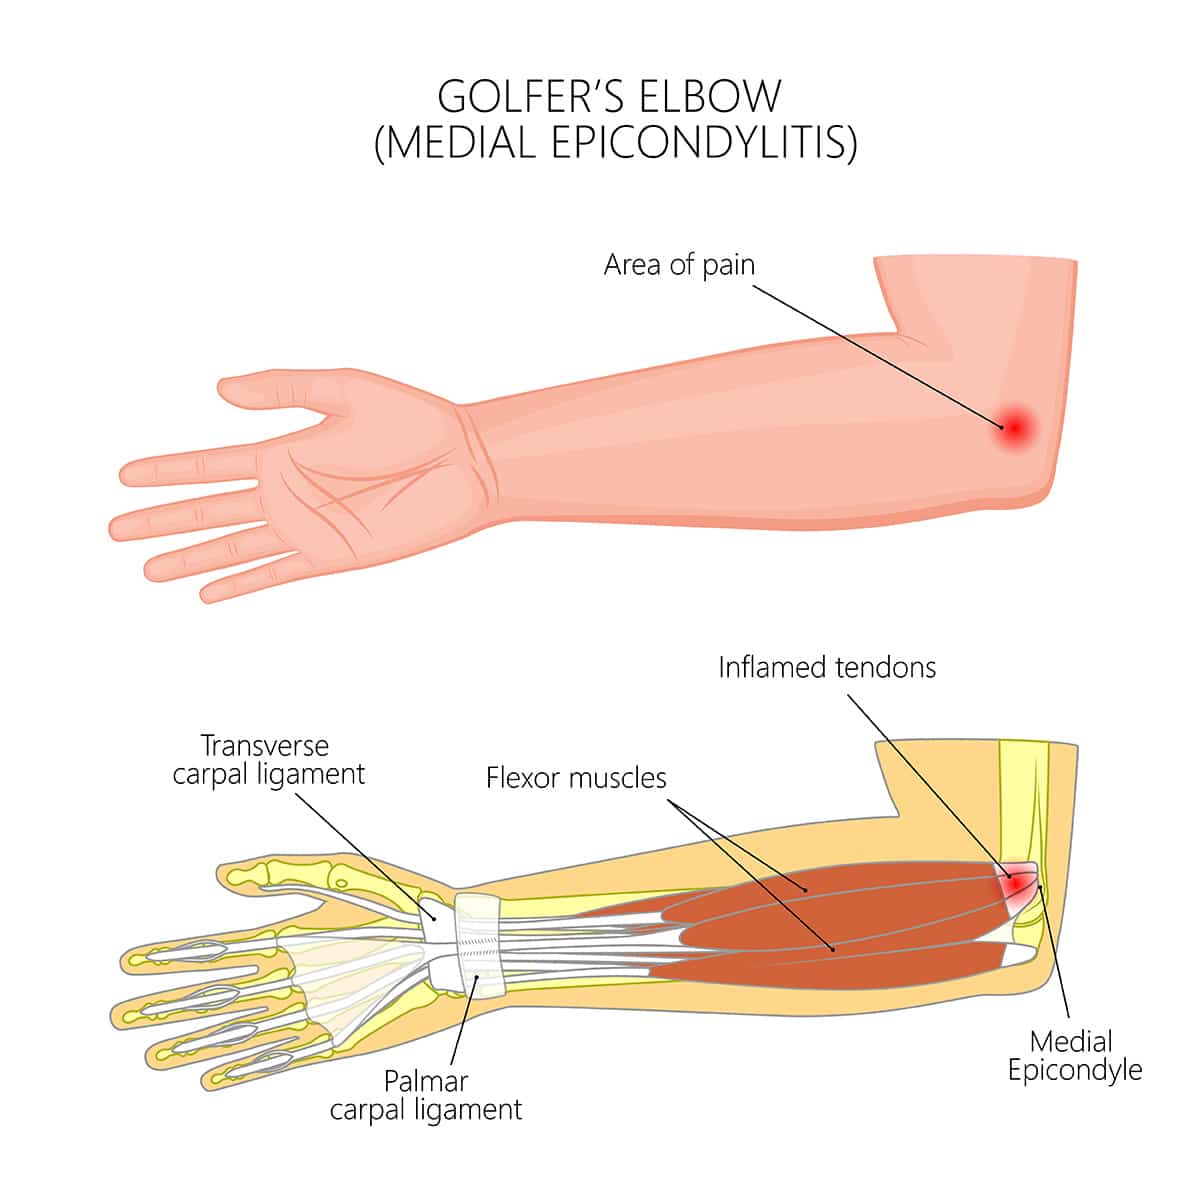

Golfer’s Elbow (Medial Epicondylitis)

Inner elbow pain due to repetitive wrist and arm movements.